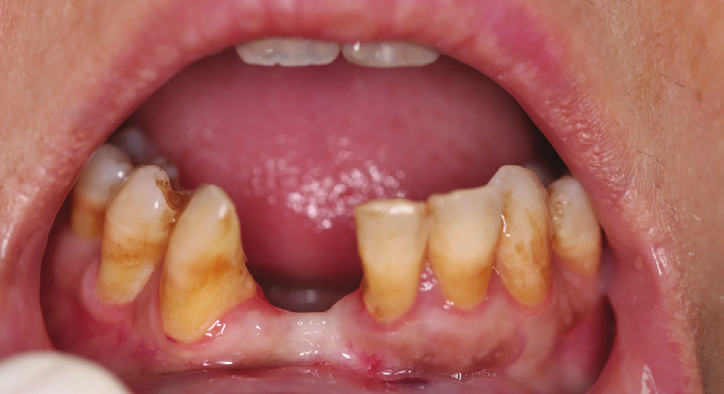

Figure 2: Intraoral view showing the extended bone and gingival loss with recession on both central incisor and canine.

Figure 3: Occlusal intraoral view showing the advanced amount of bone loss.

After removal of the bridge an extended bone loss was found. (Fig.2, 3). X-rays and CAT views were taken for the region. The amount of bone loss was extended which was an indication for autologous bone graft. A PRF associated bovine bone technique was planned. A linear incision with mucoperiosteal flap elevation was conducted. The adjacent teeth showed also bone loss (Fig.4).